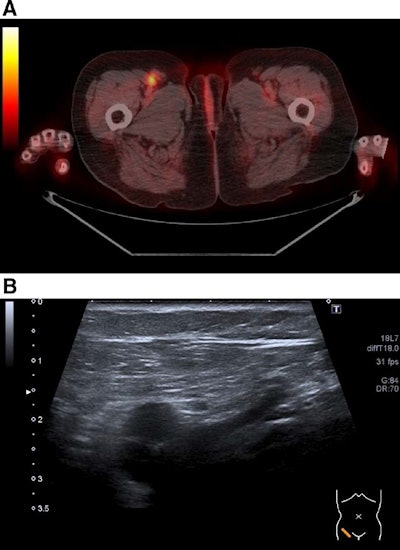

Overall, F-18 FDG-PET/CT identified 824 cancer lesions and ultrasound identified 726. On a per-exam basis, an analysis revealed significant differences for the sensitivity of F-18 FDG PET/CT (80%) compared to whole ultrasound (63%) and peripheral lymph node ultrasound (61%). PET/CT's specificity was slightly lower compared with ultrasound, however, at 96% versus 98% for whole ultrasound and 99% for abdominal ultrasound, the researchers reported.

"Based on the available data from this study, the use of [abdomen ultrasound] cannot be justified, neither as a sole application, nor in combination with F-18 FDG-PET/CT," the group concluded.